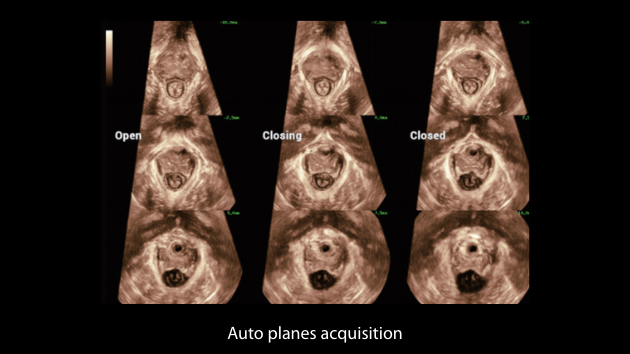

Scenario-oriented Full-stack Intelligence

The innovative Smart Scene 3D solution enables automated identification of tissue characteristics and delivers organ-specific diagnosis with full-stack intelligence throughout the entire procedure. This innovation reduces dependence on clinical skills, while elevating diagnostic accuracy, confidence, and efficiency.